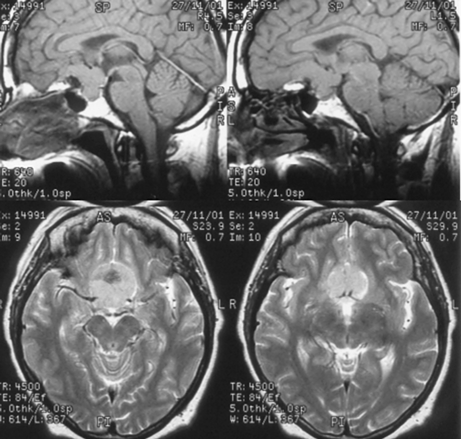

К конвекситальным относят менингиомы, исходящие из ТМО наружной поверхности мозга, не связанные с верхним сагиттальным синусом и его боковыми лакунами (рис. 1). Они составляют 23% внутричерепных менингиом и делятся по анатомическим областям на лобные, теменные, височные и затылочные. Изредка встречаются внутрикостные (интраоссальные, оссальные) и эктопические менингиомы.

Рисунок 1. Конвекситальная менингиома левой теменной области. МРТ, Т1-взвешенные изображения до (вверху) и после (внизу) контрастного усиления. Несмотря на большие размеры, опухоль не имеет отношения к верхнему сагиттальному синусу